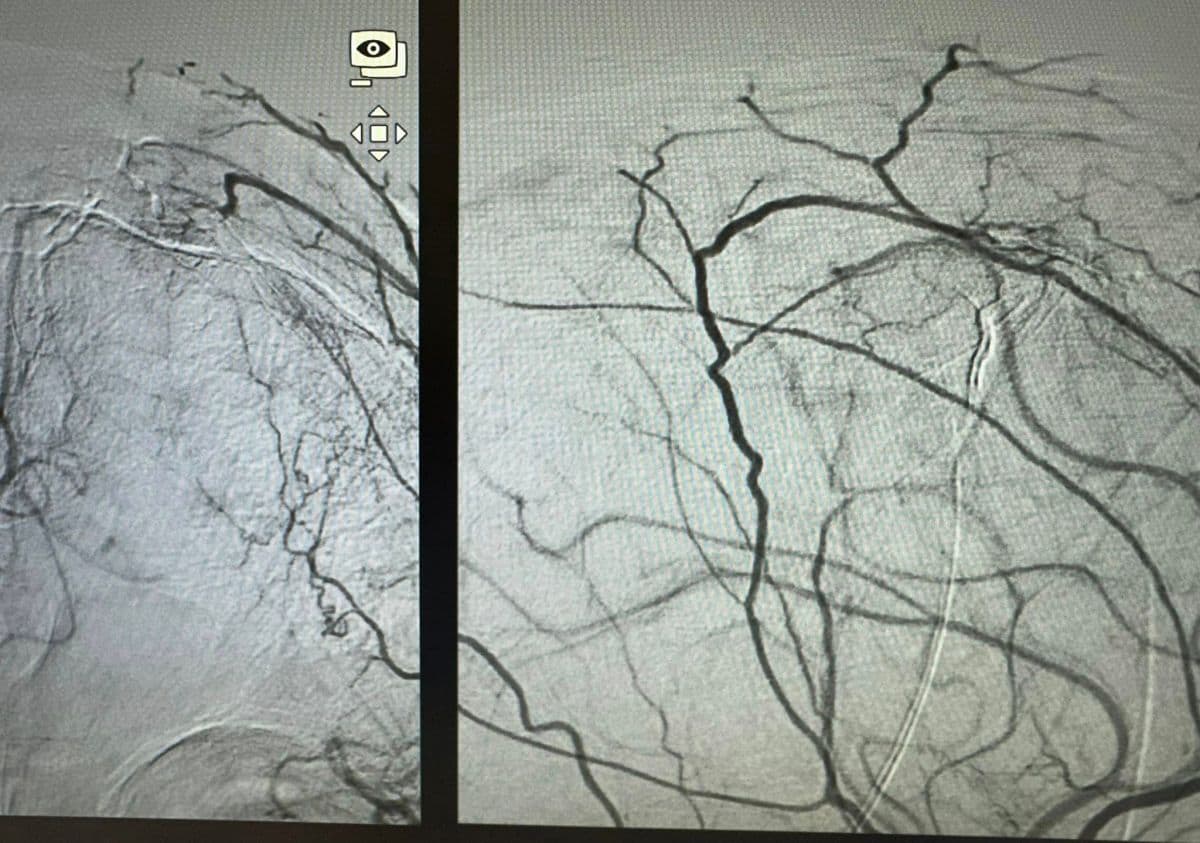

Presurgical Embolization of Brain Meningiomas reduces intraoperative hemorrhagic events and fascilitates surgical excision (Professor of Neurosurgery and Endovascular Neurosurgery V. Panagiotopoulos & Professor of Interventional Neuroradiology P. Zampakis).